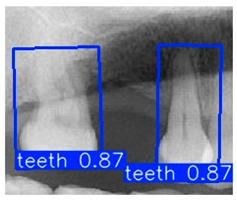

| YOLO-OBB result | ||||||

| Validation Image 1–6 | ![]() | ![]() | ![]() | ![]() | ![]() | ![]() |

| Accuracy | 84.13% 75.18% | 90.29% 76.49% | 87.38% 87.27% | 80.40% 84.48% | 70.11% 83.41% | 88.46% 76.33% |